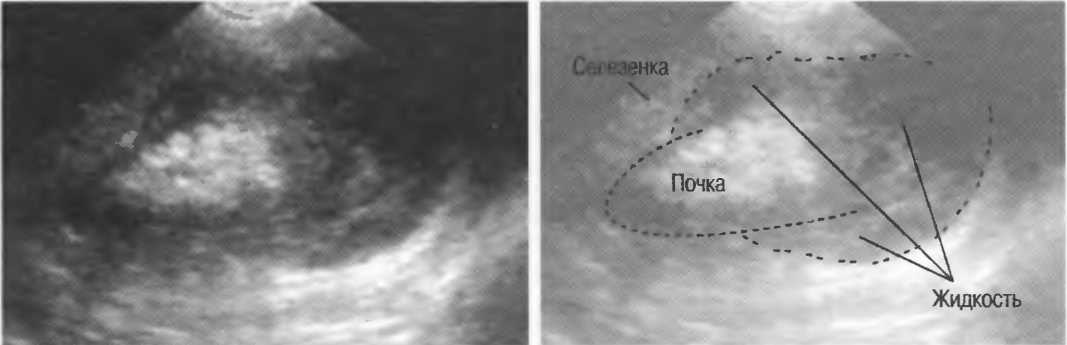

Акустическое усиление и акустическая тень

Чистые жидкости проводят ультразвуковой сигнал без существенного ослабления, поэтому отраженные эхосигналы, идущие от тканей, расположенных за жидкостью, обычно усилены (более яркие). Этот феномен известен как «акустическое усиление» (рис. 10а). Прием достаточного количества жидкости для заполнения желудка дает смещение кишечника, содержащего газ, и тем самым создает акустическое окно. Это особенно полезно для визуализации тела и хвоста поджелудочной железы.

Газ в кишечнике или еще где-либо вызывает появление различных эхографических феноменов. Ультразвуковой луч может рассеиваться, отражаться, поглощаться и преломляться таким образом, что становится практически невозможной визуализация подлежащих структур. По этой причине ультразвук не может быть использован для визуализации нормальных легких или выявления заболевания легких, за исключением объемных процессов, расположенных по периферии органа. Рентгенография грудной клетки в этом случае даст большую информацию.

Плотные материалы, такие как кости или камни, дают акустическую тень на структуры, расположенные сзади, в результате того что ультразвуковая волна не проходит через них. Этот феномен получил название «акустической тени». Например, ребра могут экранировать ультразвуковой поток, поэтому структуры, расположенные за ними, нужно исследовать в косом направлении по межреберным промежуткам (рис. 10б,в).